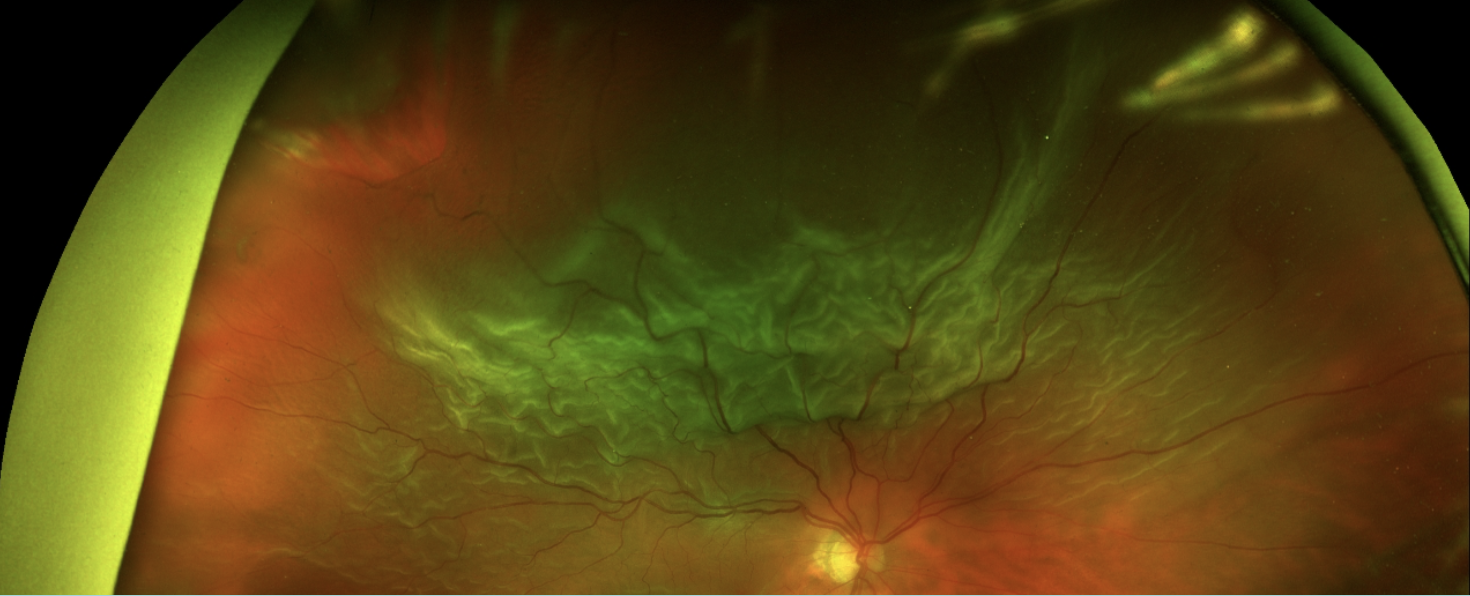

Abbildung 2: Große RA-Ablösung mit Foramen 11 Uhr